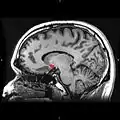

Sagittal MRI slice with highlighting (red) indicating the nucleus accumbens.